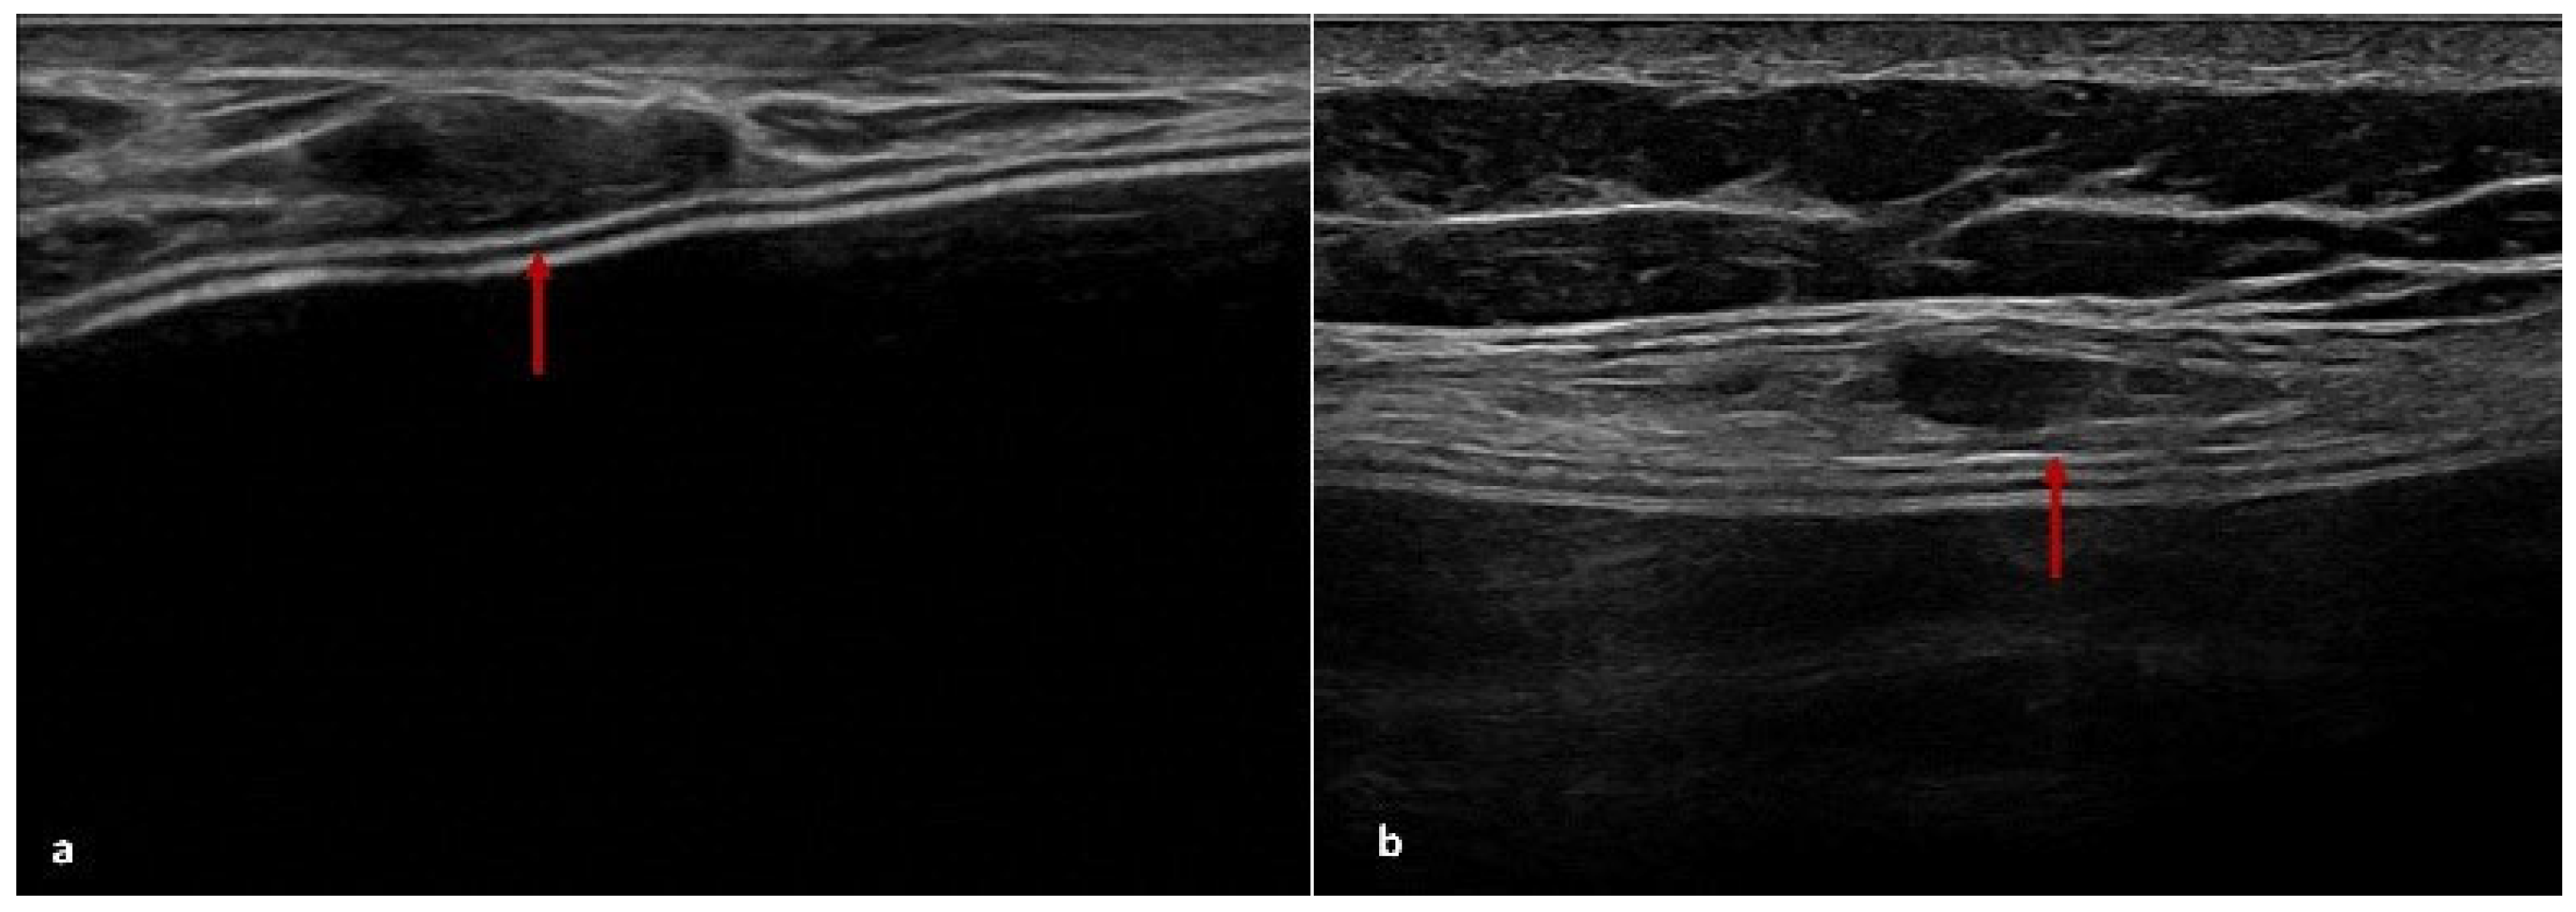

4.2. US Features of ADM

| US | Derived from pig dermis | Ten patients (16%) | Seven patients (11%) | Seven patients (11%) | Five cases of peri-capsular thickening and two cases with pseudonodular areas at T2 |